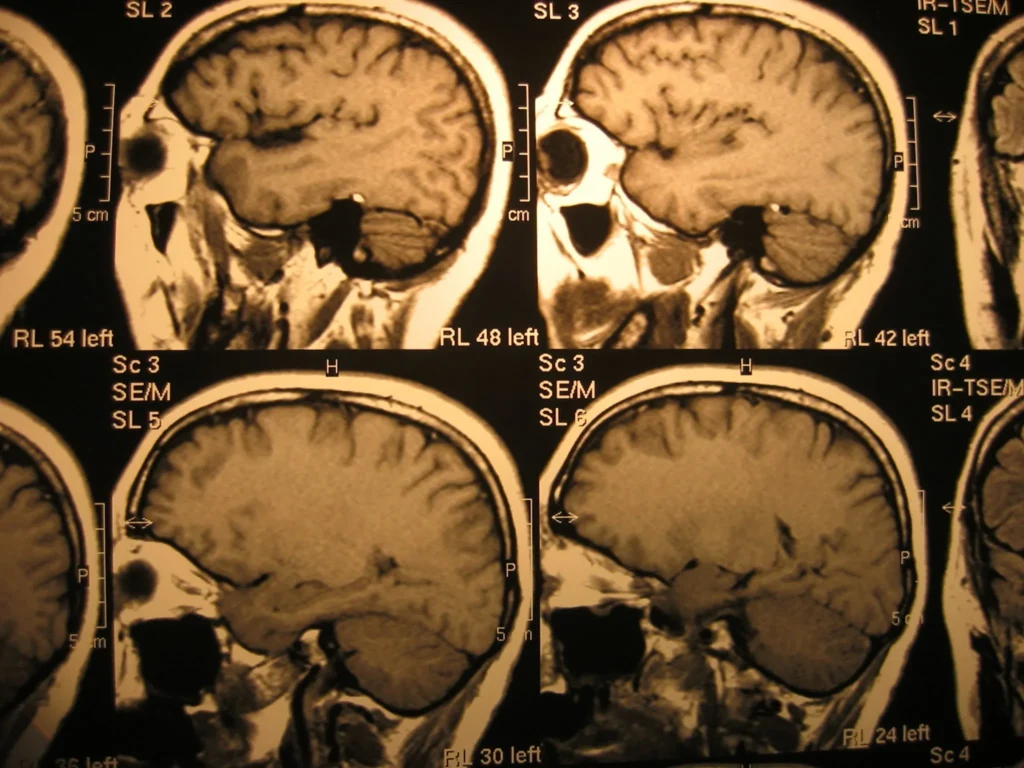

The research, led by neuroscientist Onder Albayram, examined how the brain repairs itself following repeated mild head injuries. Scientists focused on the biological systems responsible for restoring blood vessels and repairing damaged tissue.

EPA, one of the primary omega-3 fatty acids found in fish oil, is widely considered beneficial for heart and brain health. However, the study indicates that in specific cases of brain trauma, it may interfere with the brain’s natural repair mechanisms.

Researchers observed that changes in cellular energy processing could reduce the brain’s ability to recover effectively after injury.

The study also suggests a possible connection between elevated EPA levels and the buildup of proteins associated with long-term neurological conditions, including those linked to repeated head trauma.